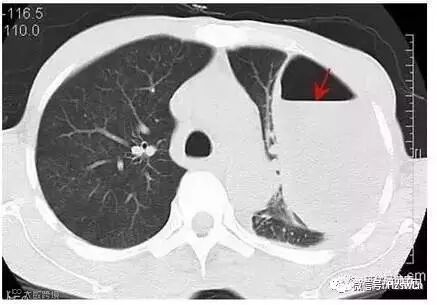

CT下的左侧包裹性胸腔积液